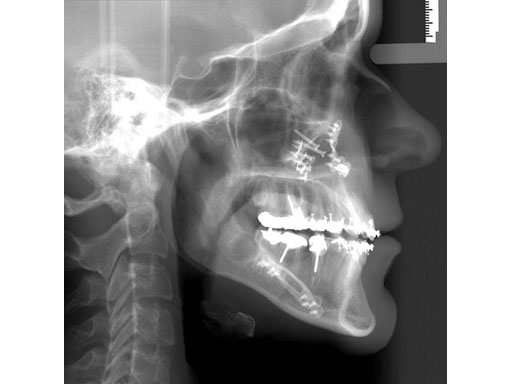

Lefort I maxillary osteotomy, bilateral sagittal osteotomies, and a genioplasty, all fixed with matrix orthognathic system used in a 19-year-old female with significant skeletofacial deformity including maxillary hypoplasia, mandibular excess, and laterognathia.

Fig 1a-c Preoperative images.